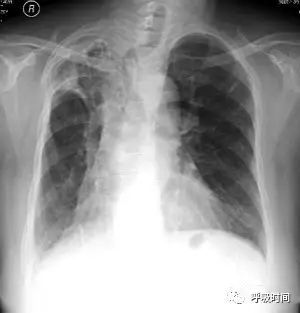

图 13 粟粒结节影——浸润性肺腺癌(细支气管肺泡癌)。双肺弥漫分布的粟粒结节影,特点:大小不一,中下肺野明显